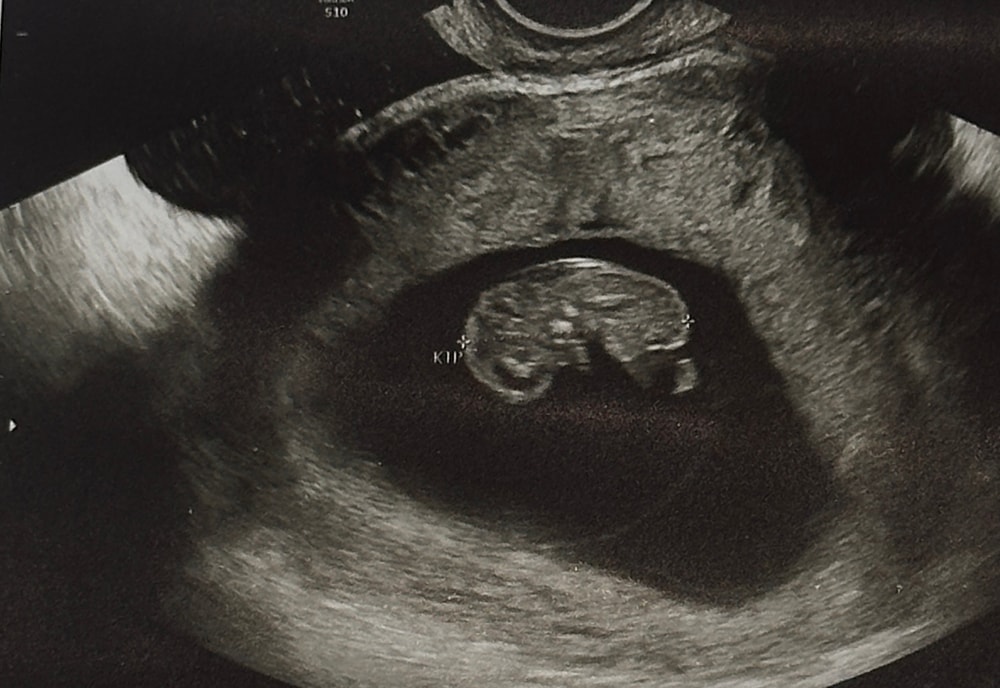

Наши будни, наши неделькиДаже не верится что ты уже на нашей

встрече такой целый человечек.

9,3 💞 а ведь ещё недавно держала тест с тенью полоской и думала «не оно»